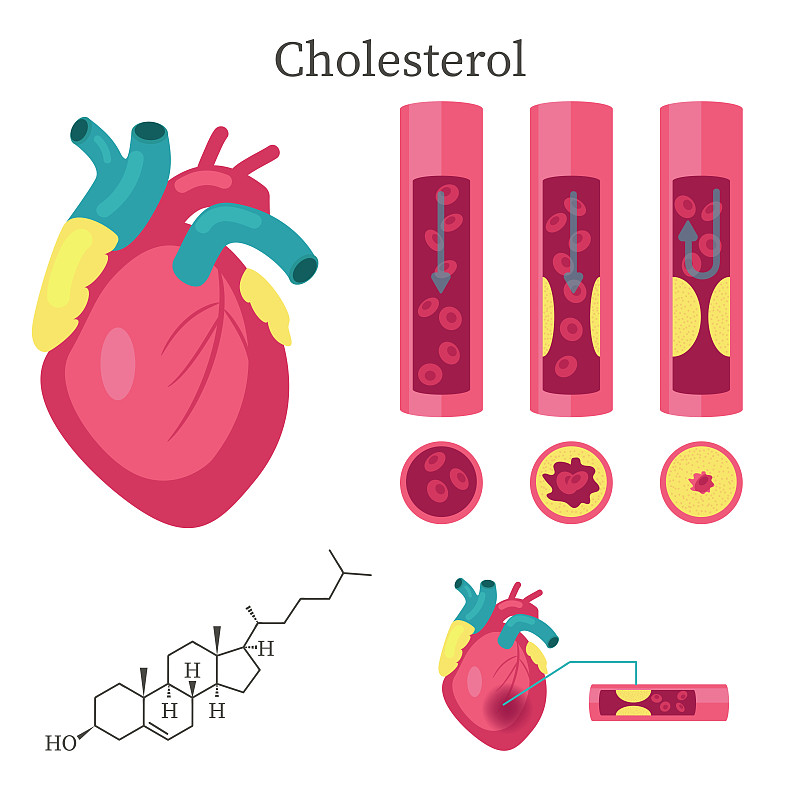

动脉粥样硬化详情

胆固醇、脂肪细胞详情